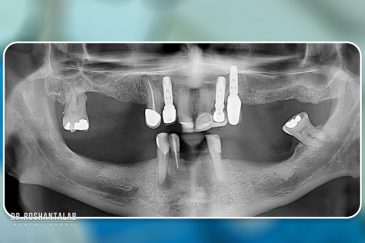

کلینیک تخصصی دکتر حسن روشن طلب با همکاری جمعی از متخصص ایمپلنت دندان و جراح فک و صورت بنام در حال فعالیت می باشد. این مجموعه مأموریت خود را ارائه خدمات تکمیلی دندانپزشکی در زمینه درمان های تخصصی و عمومی به شرح ذیل انجام می شود.

🔸 کاشت ایمپلنت دندان بدون درد

🔸کاشت ایمپلنت فلپ لس یا بدون جراحی و بدون بخیه زیر سه دقیقه

🔸 کاشت دندان یک روزه ( کشیدن و کاشت همزمان )

🔸 ایمپلنت دیجیتال و ساخت روکش دیجیتال

🔸جراحی پیشرفته نظیر سینوس لیفت

🔸ایمپلنت دندان با بیهوشی

انتخاب بهترین متخصص ایمپلنت که به تکنیکهای روز دنیا مسلط باشد، تضمینکننده سلامت فک و زیبایی لبخند شماست. در کلینیک دندانپزشکی دکتر روشنطلب، ما با بهرهگیری از تجهیزات دیجیتال در ۵ شعبه فعال (تهران، اصفهان، رشت و استانبول ترکیه)، خدمات تخصصی کاشت ایمپلنت دندان را برای بیمارانی که کیفیت و دقت برایشان اولویت دارد، ارائه میدهیم. در این متد، پروسه درمان با ظرافت بالا انجام شده؛ راهکاری ایدهآل برای کسانی که به دنبال درمان بدون درد با بالاترین نرخ موفقیت هستند.